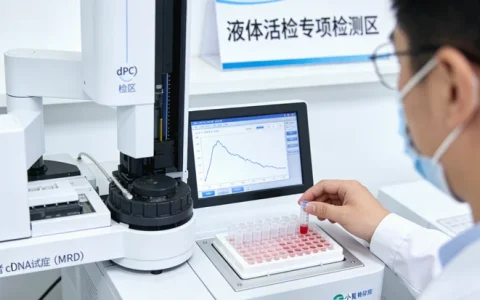

流程非常简单,远没有大家想的复杂。标准流程是:咨询了解后,在专业机构(例如,像万核基因这样的专业检测中心)签署知情同意书,然后由专业人员采集2-5毫升外周静脉血,或者使用专用的口腔拭子刮取口腔黏膜细胞。样本会由冷链专人送至中心实验室。接下来,实验室会提取DNA,使用高通量测序或基因芯片技术,对目标位点进行精准分析,并生成一份详细的解读报告。整个过程,当事人只需要配合完成采样即可。